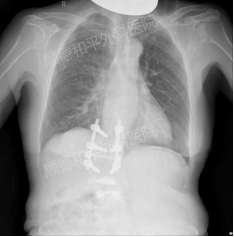

入院摄片检查可见以往内固定滞留、骨水泥强化痕迹

通过CT检查发现,患者4年前的内固定的根部位置发生了变化,牵涉到了下方的神经根,引起了腰背疼痛;而核磁影像检查时还发现其左侧骶椎有水肿(摔跤着地部位),累及到臀部、髋关节前方的大腿根部放射性疼痛。